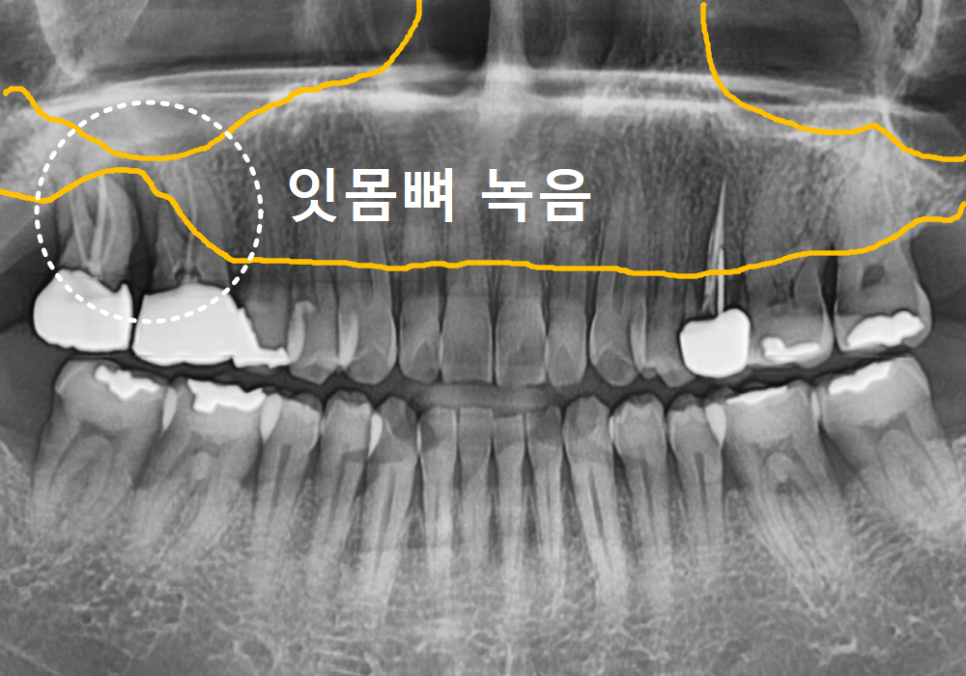

검진 결과, 치아의 동요도(흔들림)가

3도나 되었는데요.

동요도 3도란 어느 정도일까?

강동구 잇몸 퇴축으로 뿌리 드러난 치아, 이대로 둬도 괜찮을까?

치아가 앞뒤, 좌우로 흔들리는 것을 넘어

위아래로까지 툭툭 들어갔다

나왔다 할 정도로 지지력을 잃은 상태를 말해요.

사실상 잇몸뼈라는 지지 기반이

완전히 무너졌다고 보시면 됩니다.

방사선 사진 결과, 잇몸뼈 소실이 너무 심해

주변 치아까지 위험할 수 있어

안타깝지만 빠른 발치를 결정했습니다.